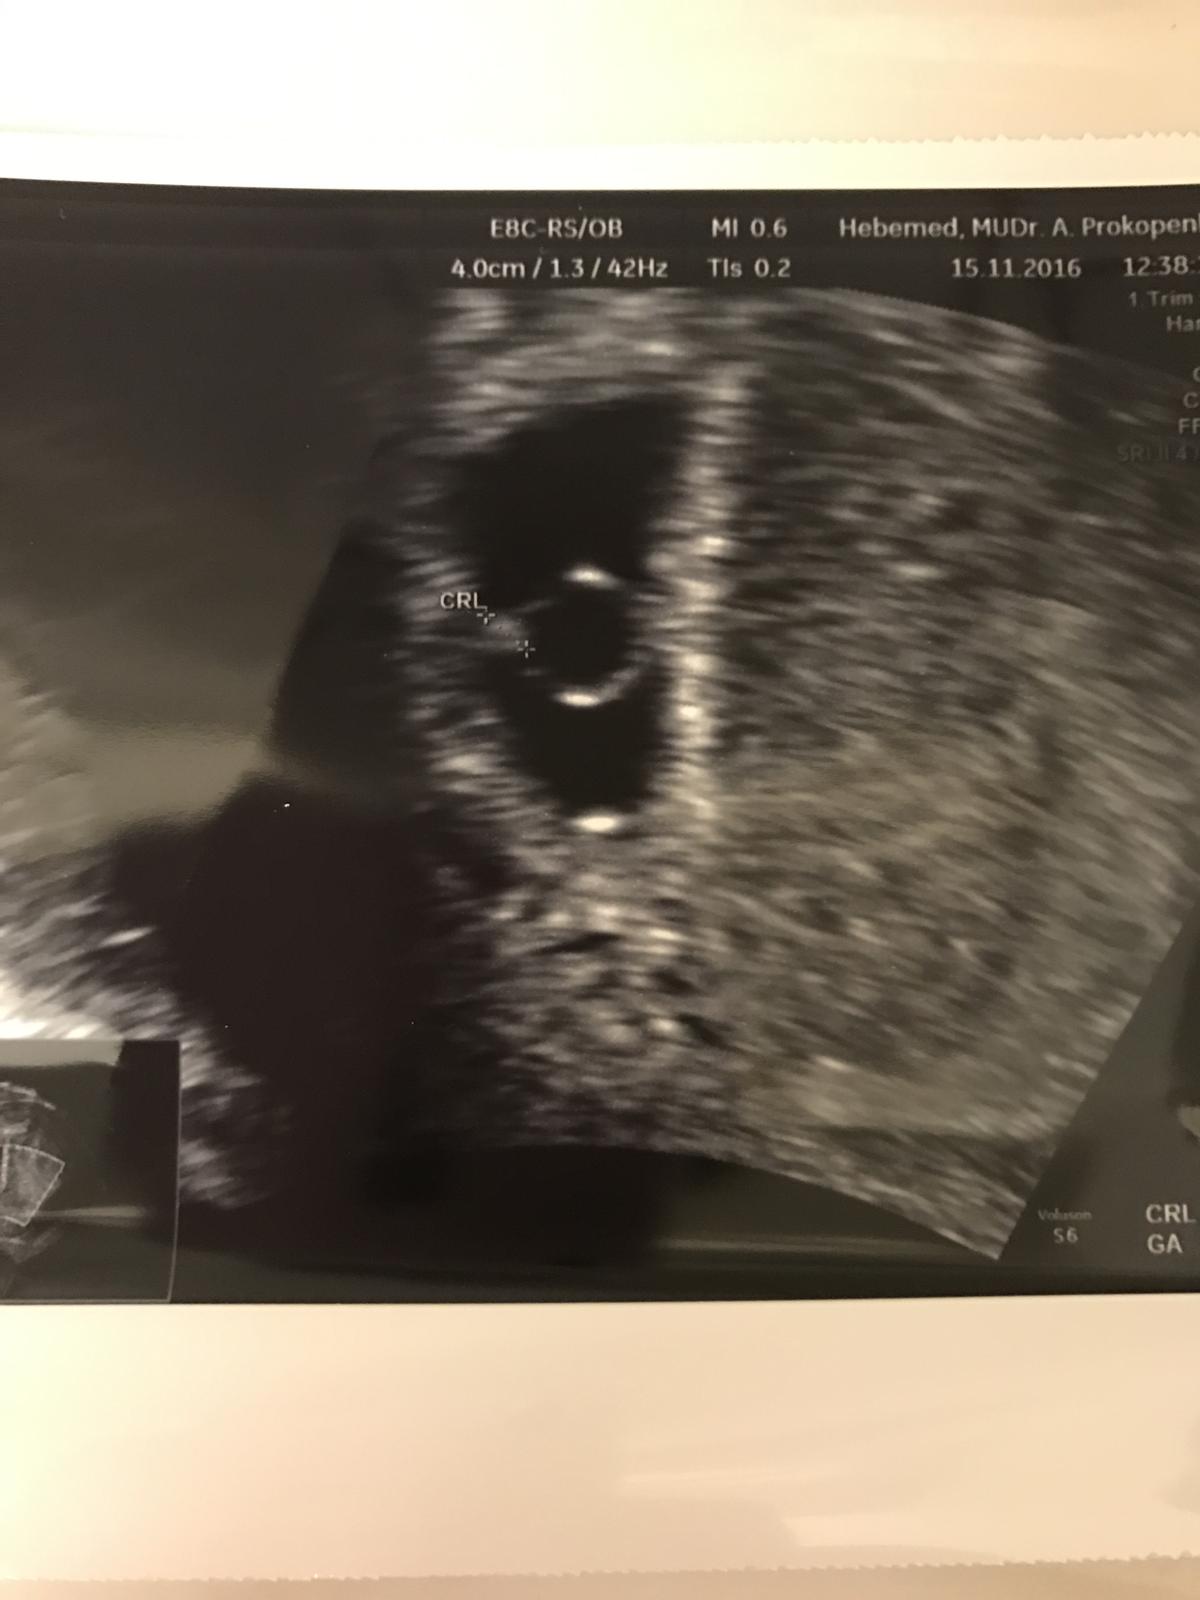

@karlos12 ale joooo.. je jeste malilinkaty vid 🙂 snad v patek bude videt vic 🙂

@lussinka88 jé, ale vždyť začalo od buněk ;) co by ses měla dovědět víc? Je to stejně nádhera, i takhle malinká. Zatím ;)

@karlos12 je to úplně neuvěřitelný.... 🙂 já nevím, takhle je vidět jen pahýl, prej už se mu začínají dělat ploutvičky a tak... 🙂) tak příště by mohl být vidět víc obrys... kamarádka už je v 10TT a viděla jak jí miminko mávalo ručičkama 🙂) no jsem zvědavá co z něho jednou bude....

@m4rtin4 jsem podle mě míň než ty 🙂)... měla bych být teď podle všeho v 6tt (konkrétně 5+3 myslím, jestli správně počítám....) zatím prej miminko odpovídá....

@lussinka88 Krásný ultrazvuk 🙂 už bych taky chtěla být v týhle fázi 🙂

@m4rtin4 to bude v pohodě. počítá se to ode dne m, ale já jsem třeba měla ovulaci až 23DC, takže by to těhu vůbec neodpovídalo.... Bylo mi řečeno, že se to stanoví až podle CRL (asi velikost miminka) v dalších týdnech... já šla na kontrolu protože jsem měla minulý týden ty křeče, jinak bych šla až teď v pátek. Jsem zvědavá jestli bobana uvidí i teď v pátek v ISCARE, protože tam maj mnohem horší ultrazvuk...